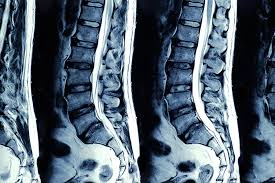

Auf dem MRT erkennt man ein deutliches Narbengewebe. Narbengewebe nach Bandscheiben-OP Zunächst sollte geklärt werden ob die Beschwerden tatsächlich vom Narbengewebe kommen. Habe vor einem Jahr Bandscheiben OP bei L45 mit anschließend 6 Wochen nicht sitzen und darauf 5 Wochen Reha gehabtDie eigentl.

Es kann vorkommen dass nach einer Wirbelsäulen OP Narbengewebe die Nerven bedrängt und das zu erneuten Schmerzen führt. Diese treten typischerweise einige Zeit nach der Operation auf Narben brauchen Zeit sich zu bilden.

Spinalkanalstenose Symptome Therapien